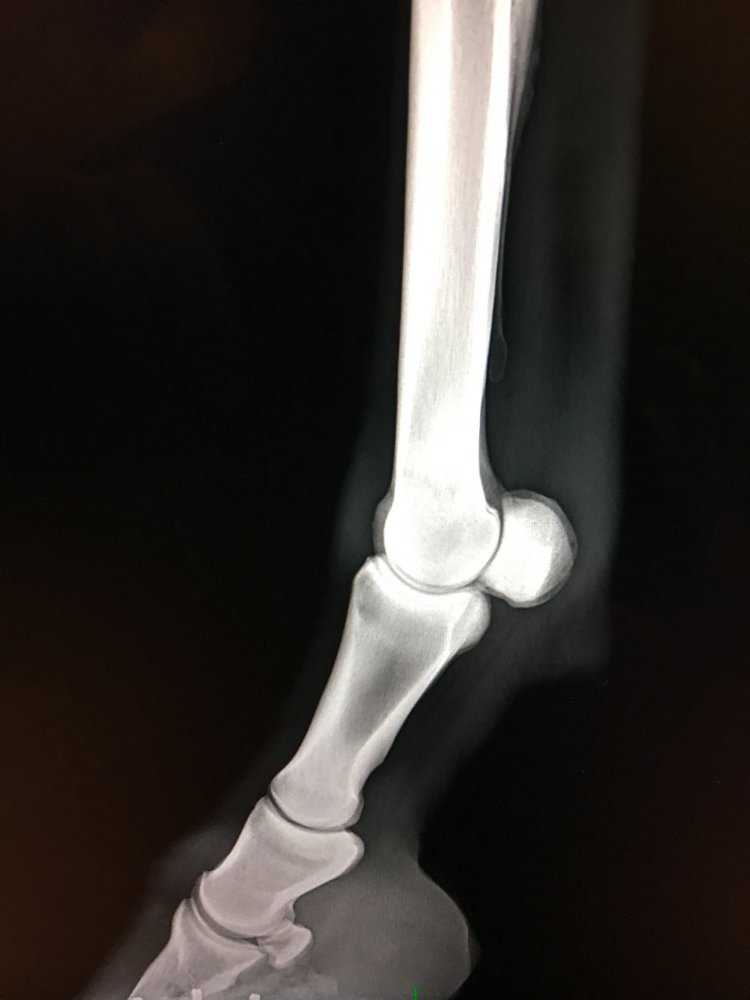

Røntgen

Jeg tilbyder røntgen af din hest med et af de nyeste digitale mobile systemer på markedet. Røntgen kan være en del af handels- eller forsikringsundersøgelsen eller relevant for at stille en diagnose ved haltheder. Har du ikke mulighed for at transportere din hest har jeg mulighed for at tage billederne hos dig, såfremt din stald opfylder nogle sikkerhedsmæssige krav mht. stråling.